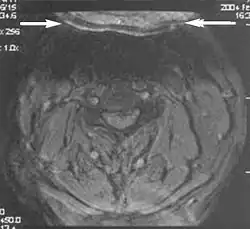

A motion artifact is one of the most common artifacts in MR imaging.[2] Motion can cause either ghost images or diffuse image noise in the phase-encoding direction. The reason for mainly affecting data sampling in the phase-encoding direction is the significant difference in the time of acquisition in the frequency- and phase-encoding directions.[1] Frequency-encoding sampling in all the rows of the matrix (128, 256 or 512) takes place during a single echo (milliseconds). Phase-encoded sampling takes several seconds, or even minutes, owing to the collection of all the k-space lines to enable Fourier analysis. Major physiological movements are of millisecond to seconds duration and thus too slow to affect frequency-encoded sampling, but they have a pronounced effect in the phase-encoding direction. Periodic movements such as cardiac movement and blood vessel or CSF pulsation cause ghost images, while non-periodic movement causes diffuse image noise (Fig. 1). Ghost image intensity increases with amplitude of movement and the signal intensity from the moving tissue. Several methods can be used to reduce motion artifacts, including patient immobilisation, cardiac and respiratory gating, signal suppression of the tissue causing the artifact, choosing the shorter dimension of the matrix as the phase-encoding direction, view-ordering or phase-reordering methods and swapping phase and frequency-encoding directions to move the artifact out of the field of interest.[1]